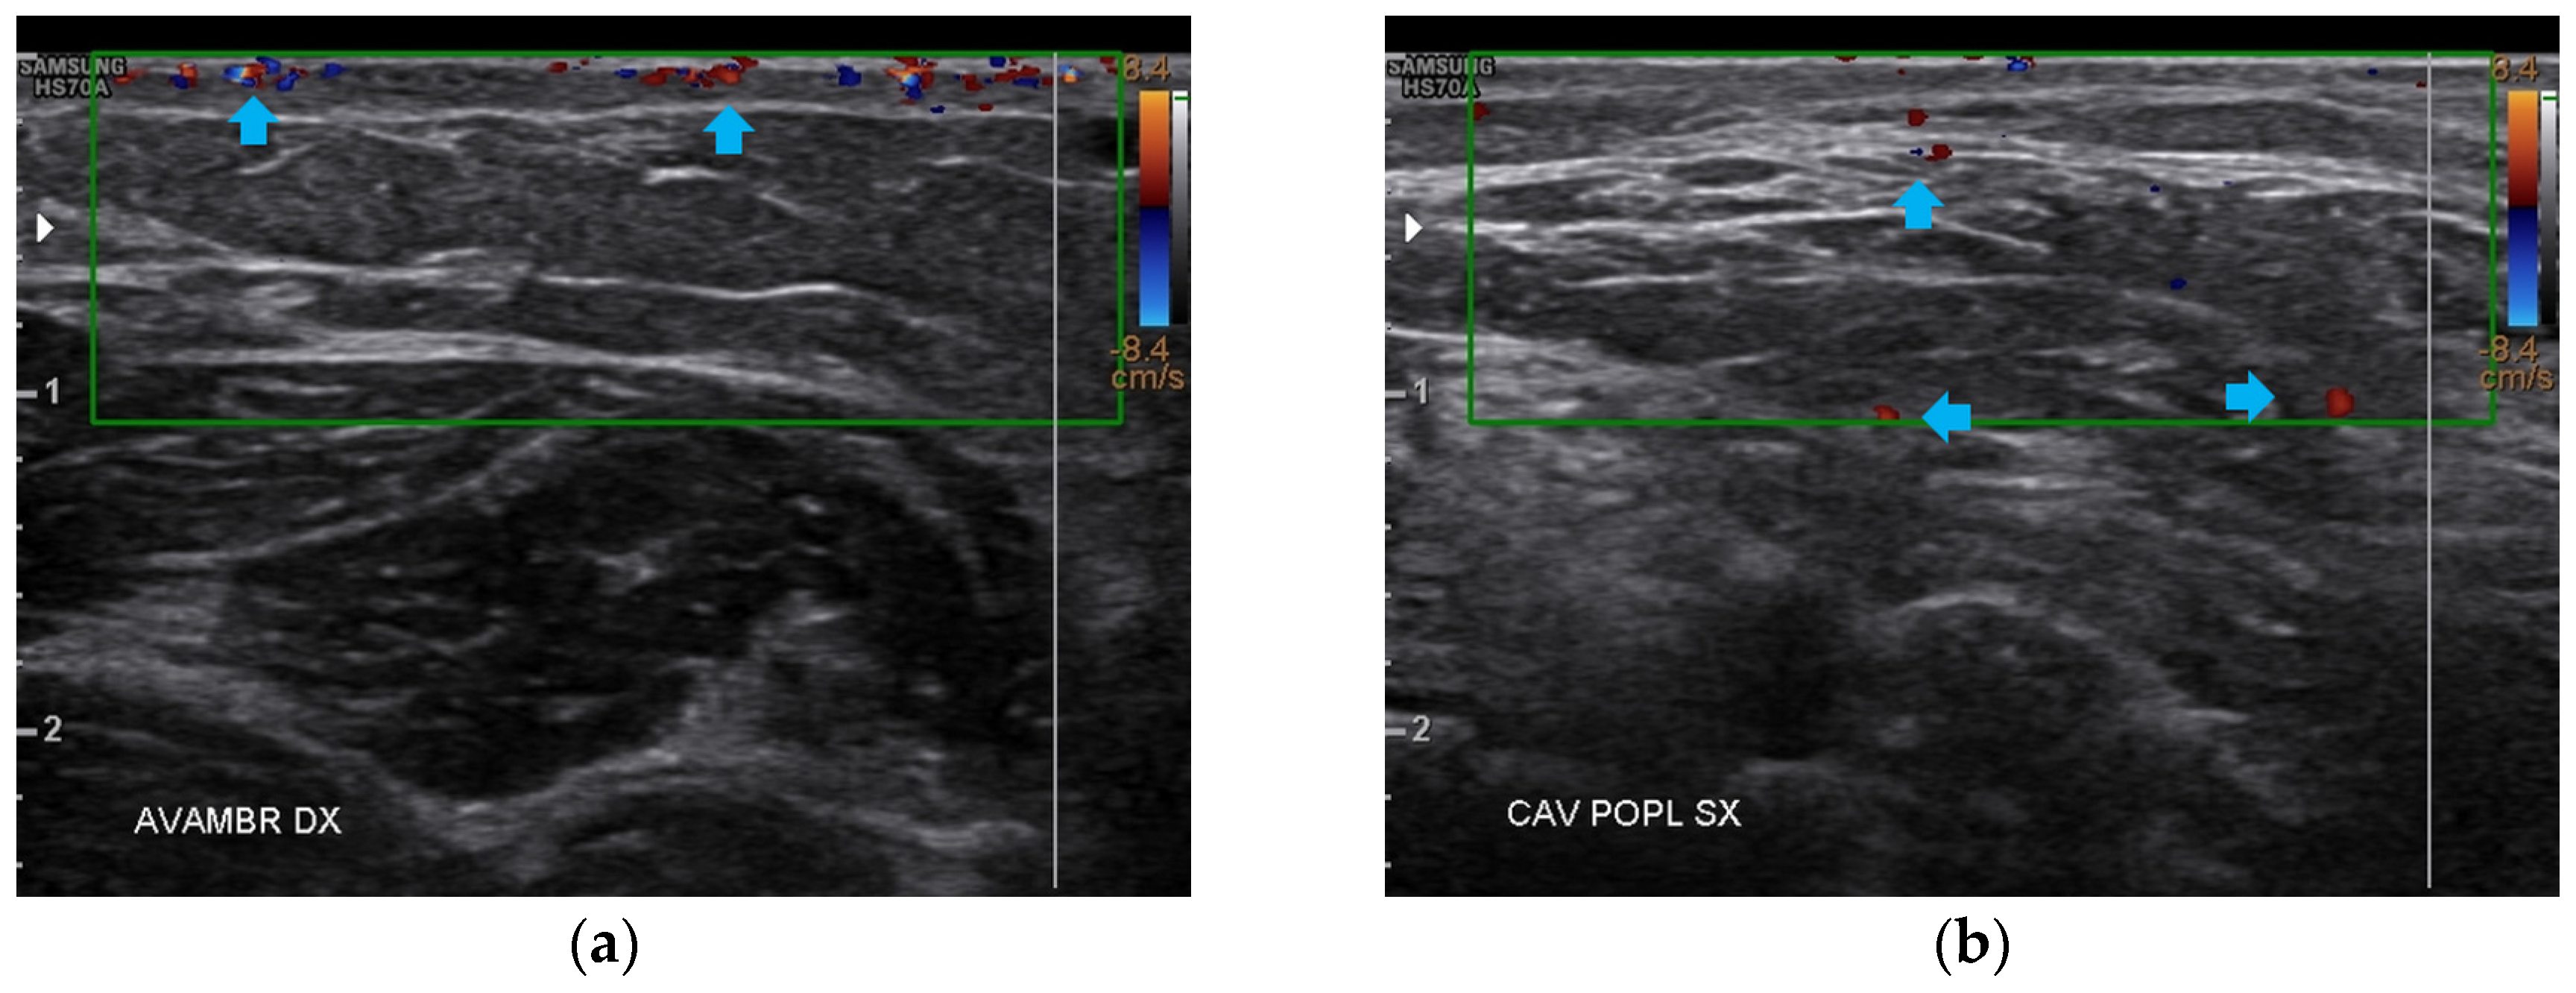

Like the forearms, the popliteal fossae, the calves, and the posterior thighs presented a clear improvement of the damaged tissues and a restructuring of the layers (Figure 7, Figure 8 and Figure 9). On the right posterior thigh, the appearance of superficial vessels was detected (Figure 9).

Figure 7.

Ultrasonography of the popliteal fossae at T1. (a) The left side presents a clear improvement in both the cicatricial fibrosis (red arrows) and the reorganization of the different structural layers (yellow arrow); (b) The right side presents the same effects of the treatment noted for the left side.

Figure 8.

Ultrasonography of the calves at T1. (a) The left side presents a clear improvement in both the cicatricial fibrosis (red arrow) and the reorganization of the different structural layers (yellow arrow). The muscular structure appears clearly defined, with a net improvement concerning the initial condition; (b) The right side presents the same treatment effects noted for the left side. On this side, the muscular structure was less compromised than that of the left side. The treatment acts on the connective tissue, softening the structure.

Figure 9.

Ultrasonography of the posterior thighs at T1. (a) On the left side, an improvement of the cicatricial fibrosis (red arrow) is clear. A restructuring of all the layers (yellow arrows) is also present; (b) The right side presents the same improvements as the left. The appearance of superficial vascular elements (blue arrows) is evident.

At T2, all four anatomical areas bilaterally presented an evident reduction of fibrosis and the restructuring of the typical layers. The appearance of both a well-diffused superficial and deep vascularization was also noted (Figure 10).

Figure 10.

Doppler ultrasound of the four areas analyzed. (a) Right forearm; (b) Left popliteal fossa; (c) Right calf; (d) Left posterior thigh. All the areas present a clear revascularization (blue arrows) extending to the deeper layers, particularly on the popliteal fossae and calves.